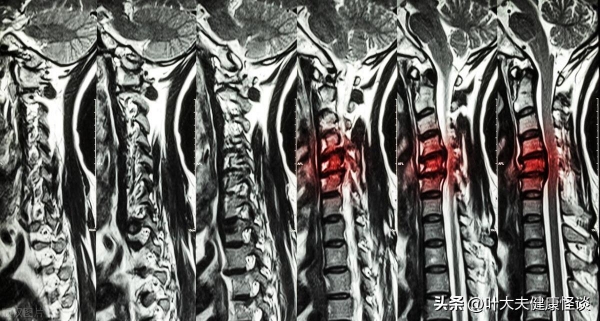

"我最近身体一直不太好,总是觉得疲乏无力,睡眠也不好,还经常头疼,去医院检查,医生说我有点轻微的失眠和颈椎病,让我注意休息,少用电子产品,多运动。"王阿姨叹了口气,语气中带着几分无奈。

"失眠和颈椎病?这可不好,你得好好注意啊!"张女士眉头紧锁,她想起自己邻居家的老张,也是因为颈椎病,后来发展成了腰椎间盘突出,现在还在医院里治疗,身体很虚弱。

缓解颈椎疼痛:艾草枕头可以缓解颈椎肌肉紧张,促进血液循环,减轻颈椎疼痛。